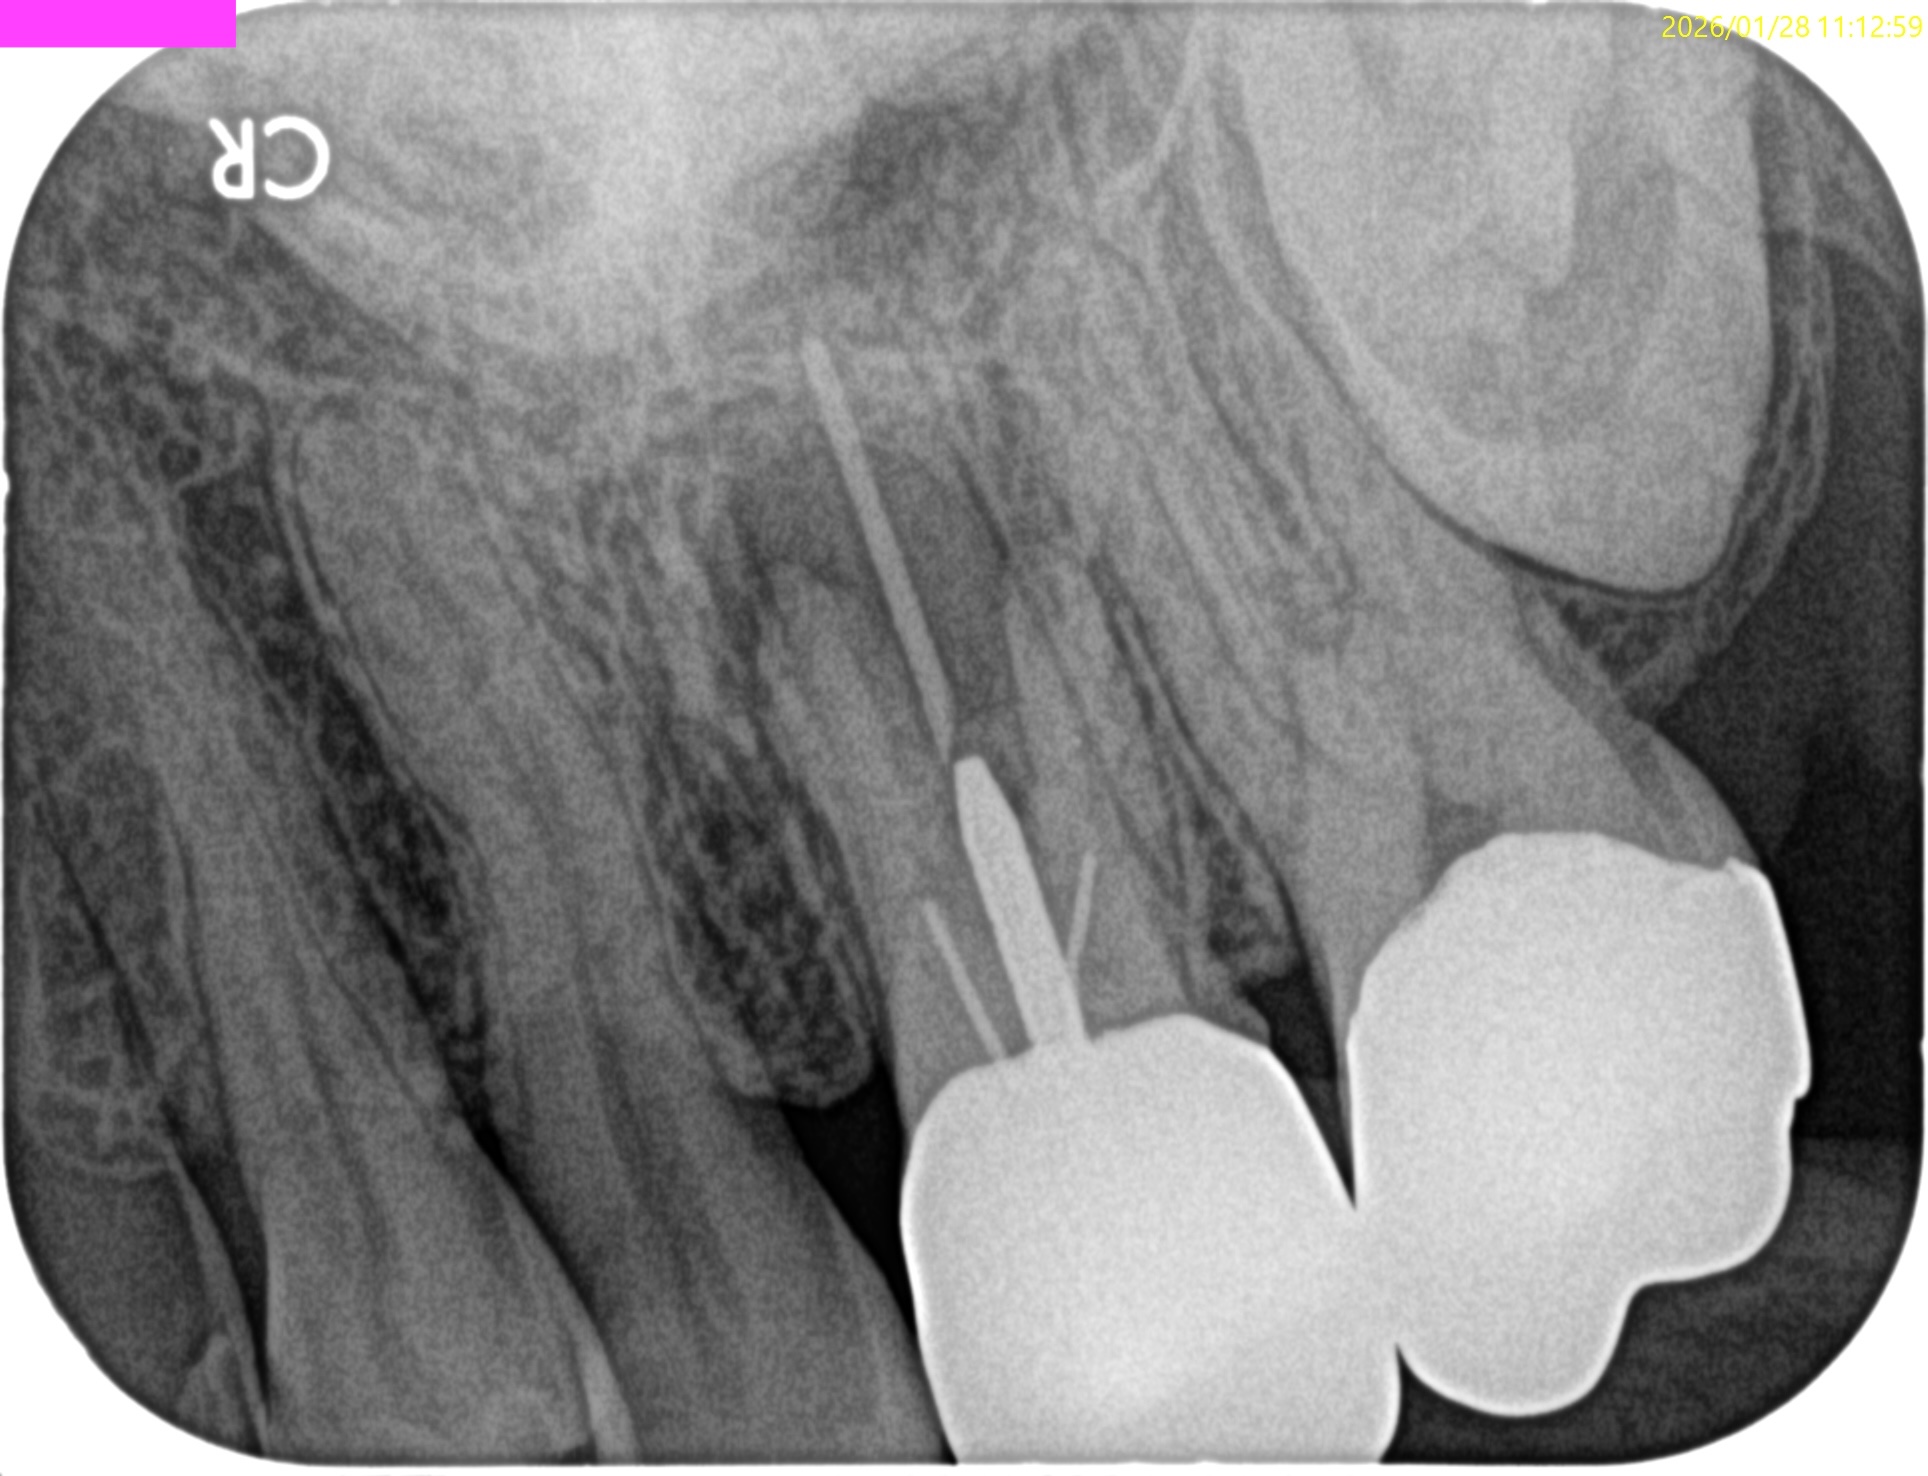

Pre-op Endo Test(2026.1.28)

MB1

MB2

DB

P

Selectiveに再根管治療をするとすれば、

MB1もしくはMB2

MB1とMB2

は穿通させる必要性があるだろう。

が、

Pはその必要があまりないだろう

ということがわかる。

MB2を発見・穿通させる必要があるかどうか?はこのように術前にCBCTを正しく分析すれば予想ができる。

MBは、

MBの作業長の予測は18~19mm(臨床的にはここからクラウンの厚み, この際はMB部分を引く必要性)ということがわかる。

DBは、

DBの作業長予測は17.4mm(ここからDBのクラウンの厚みを引いた長さ)

になろう。

が、正しくはRoot ZXが96%の可能性で正しい位置を提示してくれる。

そのためのガイドマップにCBCTは必須と言える。

MB,DBのGutta Percha Pointを除去していった。

Poorな根管充填なので容易に除去できるはずだ。

短針・ピンセットでGutta Percha Pointを除去したならば、作業長測定である。

DBから行うが、

Gutta Percha Pointの先は石灰化しているのでMunce discovery burを使用して象牙質を除去し穿通し形成した。

次がMB1である。

が、MB1は穿通しなかった。

ということは…

MB2を見つけ穿通させないといけない事態になることがここで決定する。